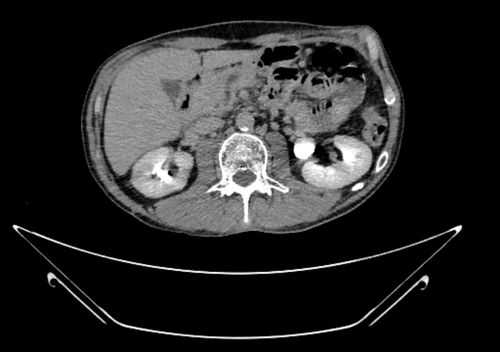

При эндосонографии (эндоУЗИ) в области головки поджелудочной железы визуализировано анэхогенное образование с четкими неровными контурами неправильной продольной формы, размерами 3,1х10 cм, прилежащее к воротной вене - постнекротическая киста с преимущественно внеорганным расположением (рис. 3).

К особенностям ситуации нужно отнести крупный размер и сложную конфигурацию кисты, ее преимущественно внеорганное расположение и близость воротной вены. Для того чтобы оценить пространственное соотношение кисты с прилежащими анатомическими структурами, а также определить наилучшее место для дренирования, была проведена 3D виртуальная компьютерная реконструкция (рис. 4).

Через 3 месяца после операции при контрольной КТ отмечена полная ликвидация кисты поджелудочной железы (рис. 8). В связи с этим стент, полностью выполнивший свою функцию, был удален.